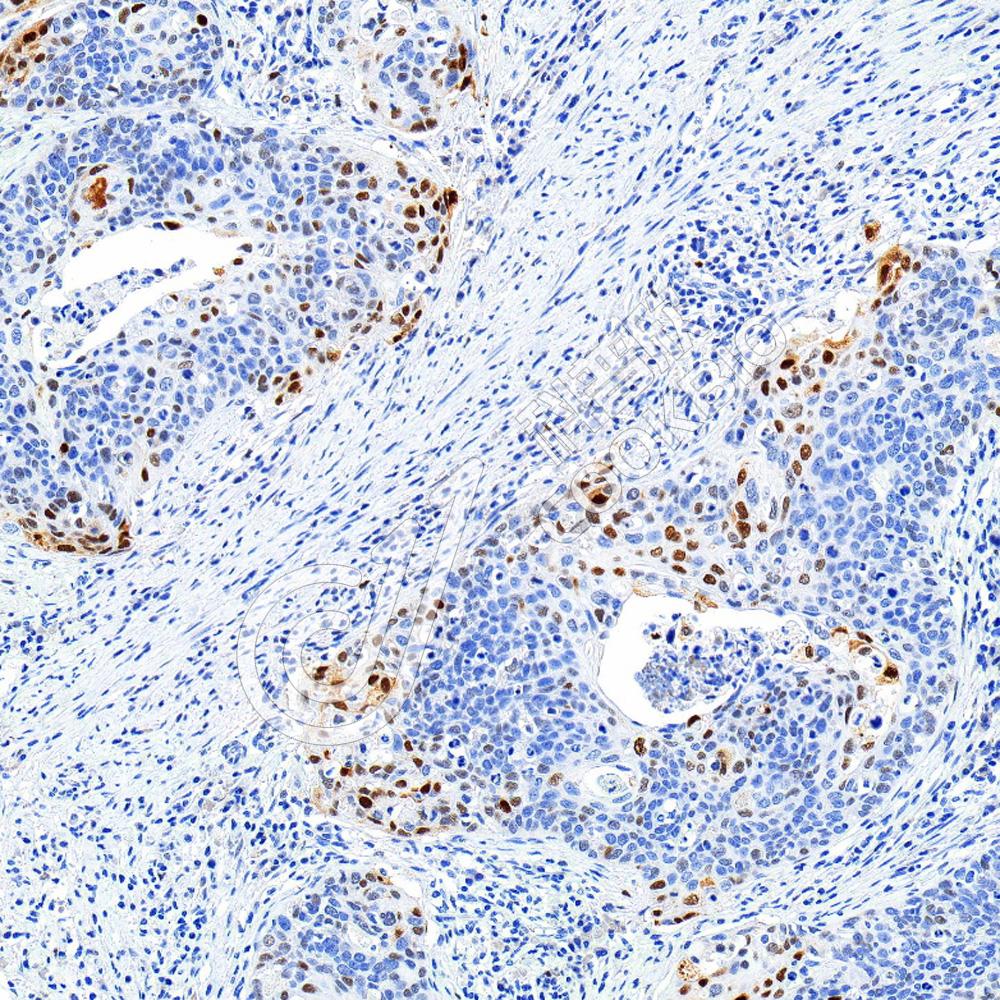

IHC检测Securin蛋白(货号 K1333141).

样品: 小鼠胎盘, 4%多聚甲醛 (货号KSG1101) 固定12-24小时.

抗原修复: 柠檬酸抗原修复液(干粉, pH 6.0) (KSG1201), 98℃, 20分钟.

—抗: 1: 1700稀释, 4℃ 孵育过夜.

二抗: S-vision免疫组化多聚二抗(山羊抗兔),即用型 (货号KB3906), 室温孵育20分钟.